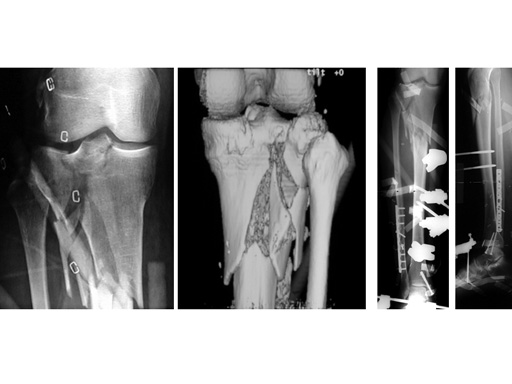

The inclusion criteria took in fractures of all degrees of severity of the proximal tibia and the tibial shaft. The fractures were classified as 110 fractures of the proximal tibia (AO 41) and 28 tibial shaft fractures (AO 42) according to the AO fracture classification system; type C fractures accounted for a total of 66% (n=91). A follow-up rate of 94% was achieved with reference to the number of fractures treated. The results of the study were evaluated immediately in close collaboration with the Principal Clinical Investigator. It is expected that the evaluation will be completed by the end of 2001; the results will be summarized and published in a final report.